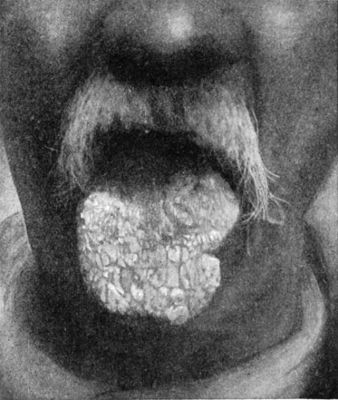

526 257.Leucoplakia of the Tongue

531 258.Papillomatous Angioma of Left Side of Tongue in a Woman